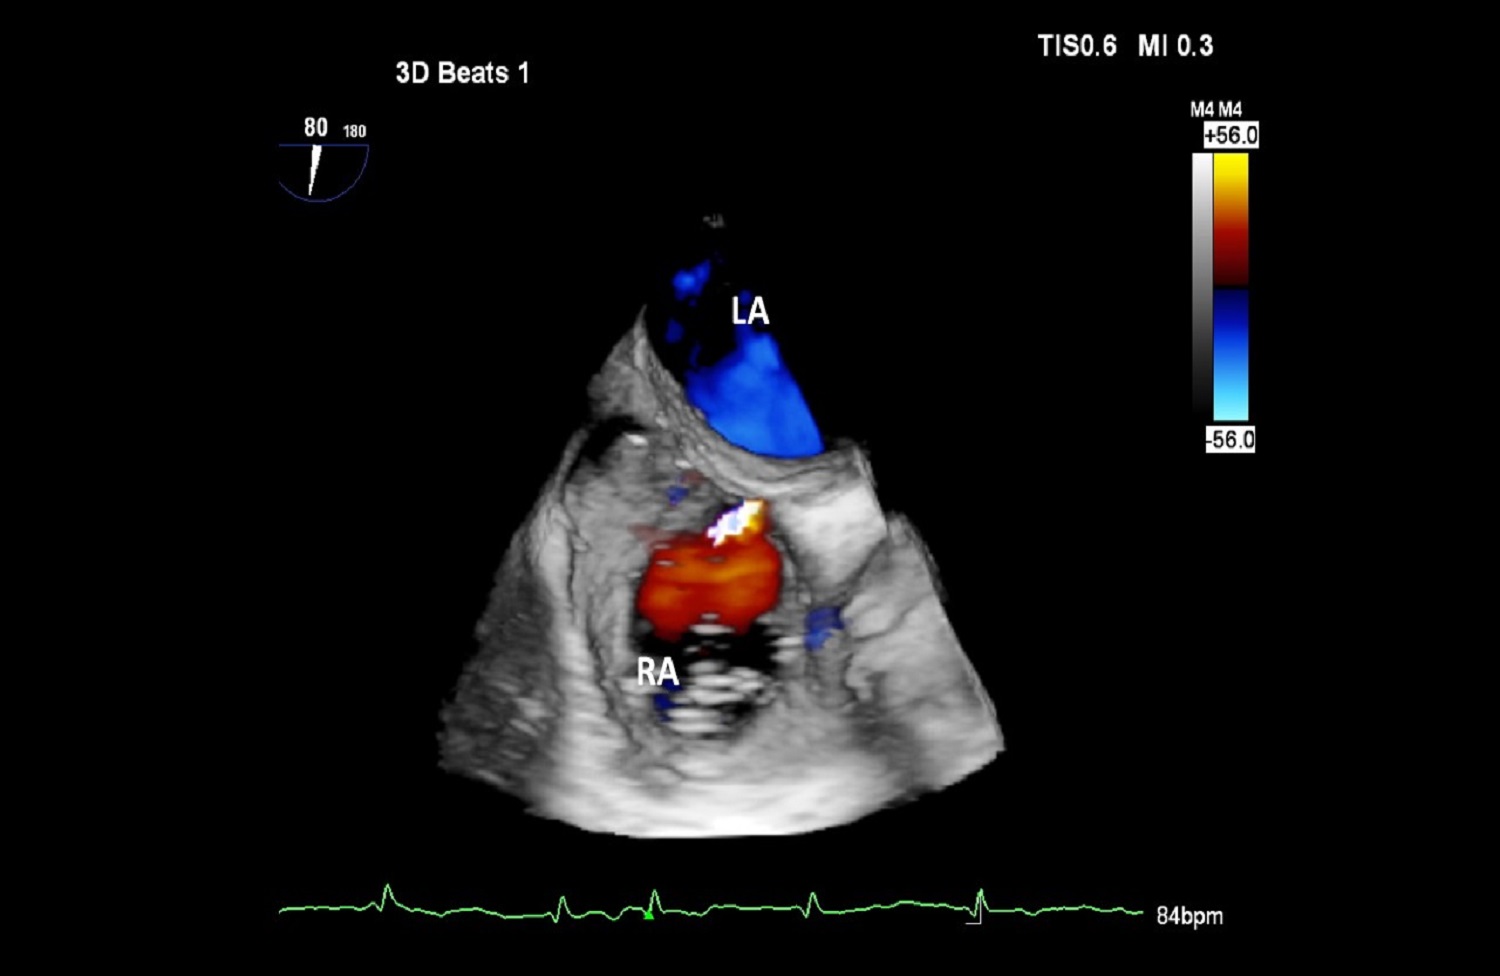

Pracownia Echokardiograficzna Kliniki posiada Akredytację Klasy C (najwyższy poziom referencyjny) przyznaną przez Zarząd Sekcji Echokardiografii Polskiego Towarzystwa Kardiologicznego. W ciągu roku wykonywanych jest tu łącznie ponad 3600 badań echokardiograficznych przezklatkowych, przezprzełykowych i prób z dobutaminą.

W Pracowni badani są pacjenci hospitalizowani w oddziałach Kliniki oraz we wszystkich pozostałych Klinikach Szpitala Klinicznego Dzieciątka Jezus, a także pacjenci ambulatoryjni kierowani z Poradni Kardiologicznej, Nadciśnienia Tętniczego, Przeciwzakrzepowej, Transplantacyjnej i Nefrologicznej Szpitala. Pracownia ukierunkowana jest na diagnostykę zatorowości płucnej, nadciśnienia płucnego, wad zastawkowych, infekcyjnego zapalenia wsierdzia oraz dysfunkcji lewej komory.

Dzięki wykwalifikowanemu personelowi i nowoczesnemu sprzętowi w Klinice wykonywane są również przezskórne zabiegi zamknięcia ubytków przegrody międzyprzedsionkowej typu II oraz drożnego otworu owalnego, pod kontrolą echokardiografii dwu – i trójwymiarowej.

Na podstawie badań z zastosowaniem przezprzełykowej echokardiografii trójwymiarowej w pracowni kwalifikuje się również pacjentów z ciężką niedomykalnością mitralną w mechanizmie wypadania płatka mitralnego do nowatorskich zabiegów małoinwazyjnej przezkoniuszkowej naprawy zastawki bez użycia krążenia pozaustrojowego. Efektem współpracy z Oddziałem Kardiochirurgii Szpitala Medicover była możliwość monitorowania echokardiograficznego przezprzełykowego dwóch pierwszych w Polsce zabiegów naprawy zastawki mitralnej z użyciem robota chirurgicznego da Vinci.

Echokardiografia przezklatkowa przezprzełykowa obciążeniowa z pełnym obrazowaniem dopplerowskim i trójwymiarowym.